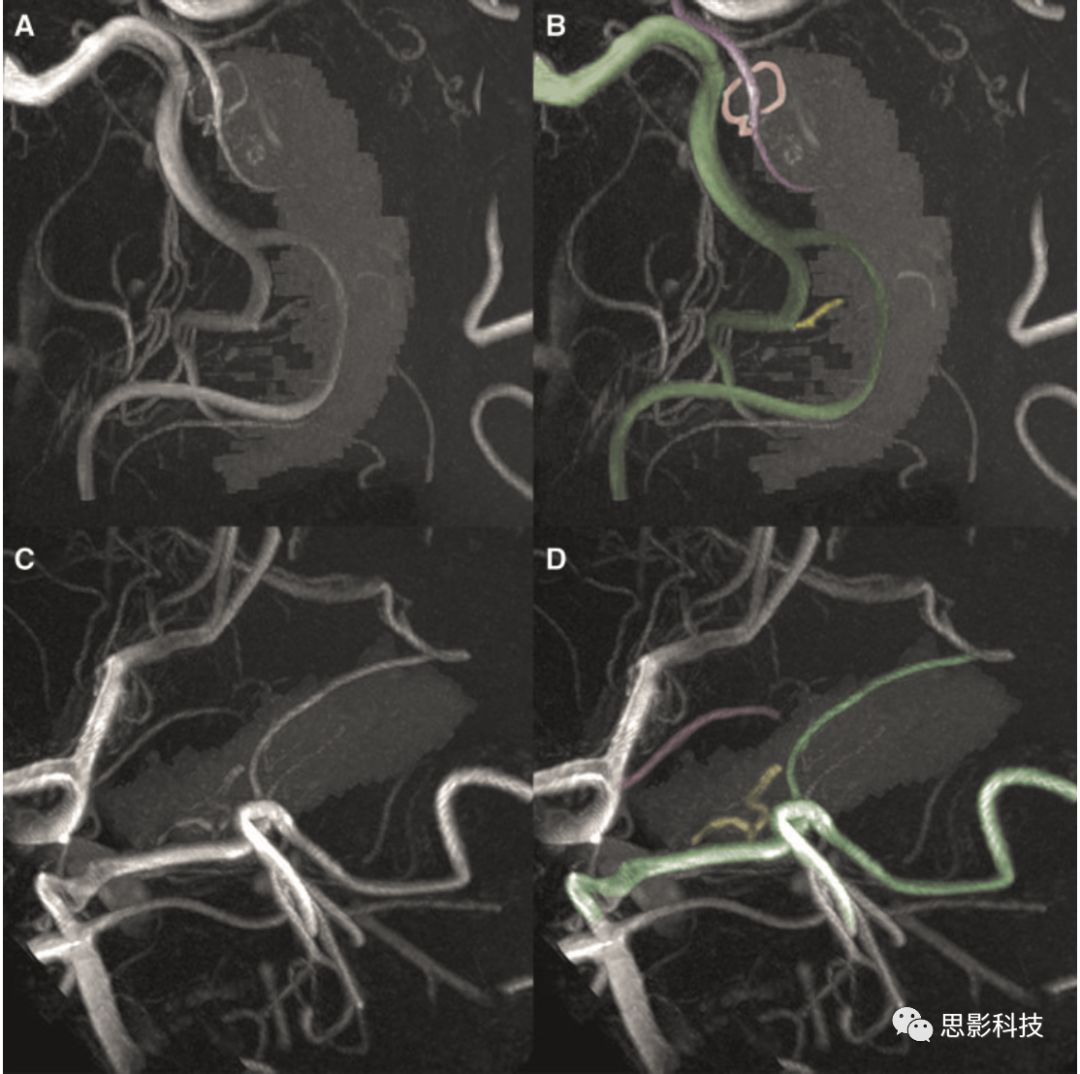

首先通過MRIcron軟件包內(nèi)的dcm2nii7T T1以及TOF DICOM格式數(shù)據(jù)轉(zhuǎn)為NIFTI格式。然后T1圖像在SPM12內(nèi)進(jìn)行處理。為確定海馬血管模式,首先需要制定每個被試的海馬mask。本研究通過FreeSurfer 6.0進(jìn)行自動分割,提取雙側(cè)海馬并獲得其體積,同時也獲得顱內(nèi)總體積。接下來,海馬mask以及T1均配準(zhǔn)到TOF上(使用Advanced Normalization Tools,ANTs)。為了清楚辨認(rèn)海馬血管供應(yīng)模式,利用MeVisLabTOF成像進(jìn)行處理達(dá)到最大強度投影。如果觀察到脈絡(luò)膜前動脈末端分支穿過海馬區(qū)域,則判定為海馬混合血管供應(yīng)模式。因為同一個體雙側(cè)海馬血管也存在變異,所以研究者利用海馬血供評分進(jìn)行分組,Group 0表示雙側(cè)海馬均為單血管供應(yīng)模式,Group 1表示至少一側(cè)為海馬混合血管供應(yīng)模式(圖1)。本研究共47例被試,所以探討了94個海馬,其中只有85個海馬可以識別其血管模式。剩下來的9個海馬血供模式存在疑問,可能由于偽差或者吻合口小血管混淆。

1AB圖為海馬混合血管供應(yīng)模式。圖中綠色的血管代表大腦后動脈,黃色血管為其供應(yīng)海馬的分支,紫色血管為脈絡(luò)膜前動脈,粉色血管為其發(fā)出的分支,可以明顯看到大腦后動脈與脈絡(luò)膜前動脈均為海馬供血。而CD圖為海馬單血管供應(yīng)模式,僅有大腦后動脈分支進(jìn)行供血,未見脈絡(luò)膜前動脈發(fā)出分支供血。